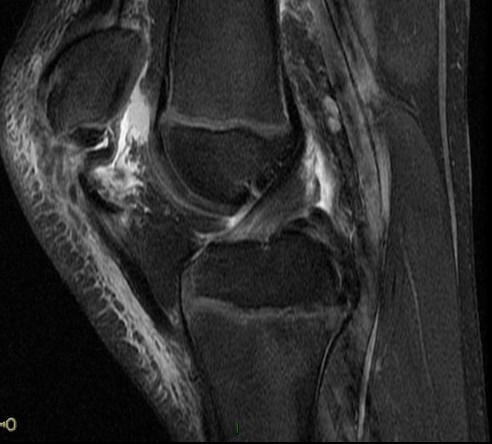

Trampoline injury, 10y/o

Wheeless: mechanism: eccentric contraction of the quadriceps on the flexed knee. occurs when the inferior pole of the patella of a child or adolescent is pulled off together with a large amount of articular cartilage and retinaculum. Superior patella pulled superiorly with chondral defect. Reference article.

Patellar sleeve avulsion